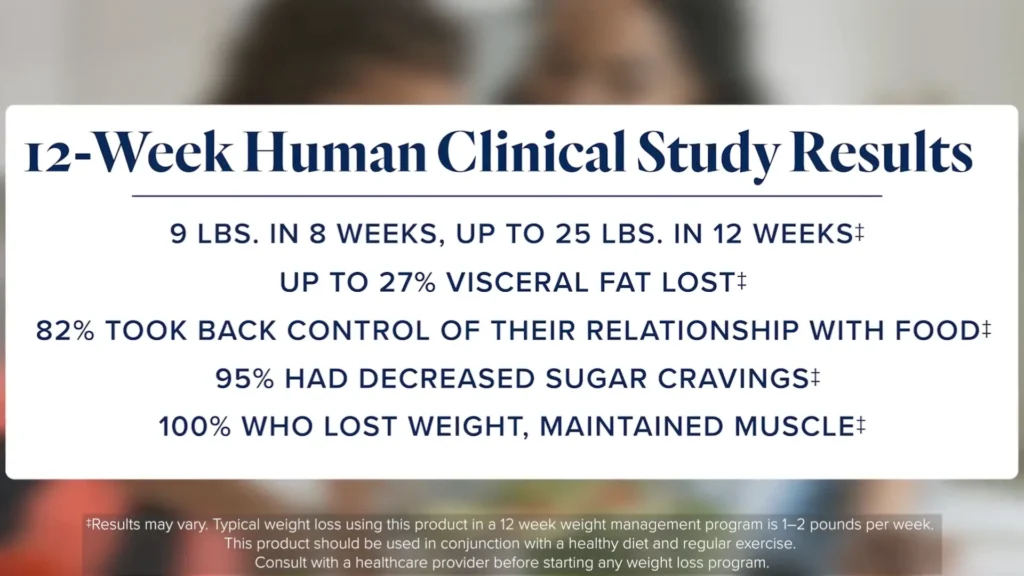

Equilibre las hormonas del hambre, construya mejores hábitos y alcance su peso saludable con un potente sistema de 2 productos que utiliza la activación dual para aumentar el GLP-1 y disminuir el ruido de la comida.* Aumente el GLP-1 en un promedio de 140% con un sistema de 2 productos pendiente de patente. Resultados basados en un estudio clínico aleatorizado de 12 semanas en humanos. Contenido: MB Core™ 60 cápsulas, MB Enhance™ suministro para 30 días Beneficios del sistema GLP-1 de LifeVantage MindBody: Aumenta Naturalmente el GLP-1 Ω Apoya la pérdida de peso sostenible y el bienestar para obtener resultados que puedes ver y sentir. *Ayuda a equilibrar las hormonas del hambre para aumentar la saciedad a través del eje...

Equilibre las hormonas del hambre, construya mejores hábitos y alcance su peso saludable con un potente sistema de 2 productos que utiliza la activación dual para aumentar el GLP-1 y disminuir el ruido de la comida.* Aumente el GLP-1 en un promedio de 140% con un sistema de 2 productos pendiente de patente. Resultados basados en un estudio clínico aleatorizado de 12 semanas en humanos. Contenido: MB Core™ 60 cápsulas, MB Enhance™ suministro para 30 días Beneficios del sistema GLP-1 de LifeVantage MindBody: Aumenta Naturalmente el GLP-1 Ω Apoya la pérdida de peso sostenible y el bienestar para obtener resultados que puedes ver y sentir. *Ayuda a equilibrar las hormonas del hambre para aumentar la saciedad a través del eje...